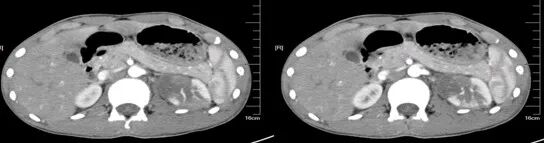

升结肠癌并广泛转移

气腹管怎么接肠梗阻、肠套叠、气腹、肝挫伤、脾挫伤、肾挫伤、胰腺损伤、食管癌、胃肠肿瘤_https://www.jmylbn.com_新闻资讯_第49张

气腹管怎么接肠梗阻、肠套叠、气腹、肝挫伤、脾挫伤、肾挫伤、胰腺损伤、食管癌、胃肠肿瘤_https://www.jmylbn.com_新闻资讯_第50张

升结肠癌